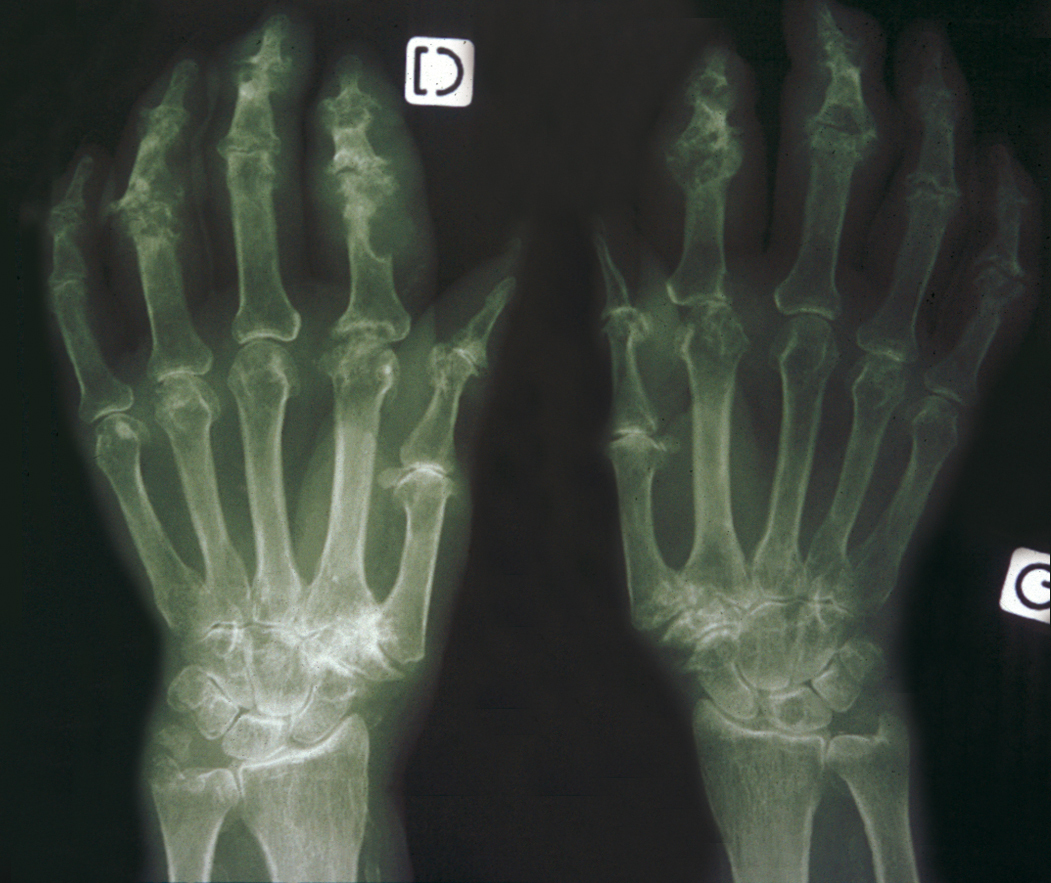

Elle est à un stade avancé ici. La goutte tophacée peut avoir un potentiel destructeur à la fois articulaire et osseux. Même si la radiographie est utile au diagnostic différentiel et peut montrer des aspects typiques de goutte chronique, elle n'est pas utile pour confirmer le diagnostic de goutte aiguë ou récente. Au cours de la goutte chronique, les radiographies permettent de déceler des modifications ostéocartilagineuses asymétriques (mains, pieds, poignets, coudes, genoux), secondaires à la réaction inflammatoire autour des tophus, comportant :

- des érosions osseuses caractéristiques : encoche épiphysaire avec un éperon osseux (aspect en hallebarde) ;

- comme ici une image d'empreinte dans les parties molles (augmentation de la densité des parties molles dues au tophus) très évocatrice de goutte chronique ;

- un interligne tardivement conservé jusqu'au stade de goutte chronique et l'absence de raréfaction osseuse périarticulaire permettant de différencier la goutte d'autres arthropathies ;

- comme ici une destruction des interphalangiennes proximales et distales.